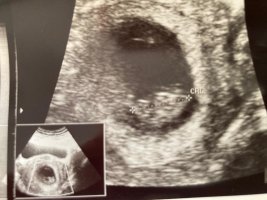

Tekrar merhabalar bugün doktordan geldim ve sizinle tekrar paylaşmak istedim yorumlarmısınız cook teşekkür ederim fazla yükledim ki siz karar verin

Malesef hayatım resmin resmini çekerken net çekemiyorsun gen eyorum yapamıyorum gene kız gibi görünüyor diyebilirim nuba göre 🙂

Yok bi tanem bu küçük sıpagettinin cinsiyetini çok net göremiyorum. Hem takılma bunlara sen. Çok net görsek te, vereceğimiz bilgi net değil 🙂 Kız gibi gördük öyle dursun bakalım güzelleşsin serpilsin net görüntü elbet gelecektir. Rabbim sen ve senin gibi anne olmak üzere olanların gönlündekini nasip etsin inşAllah 🙂